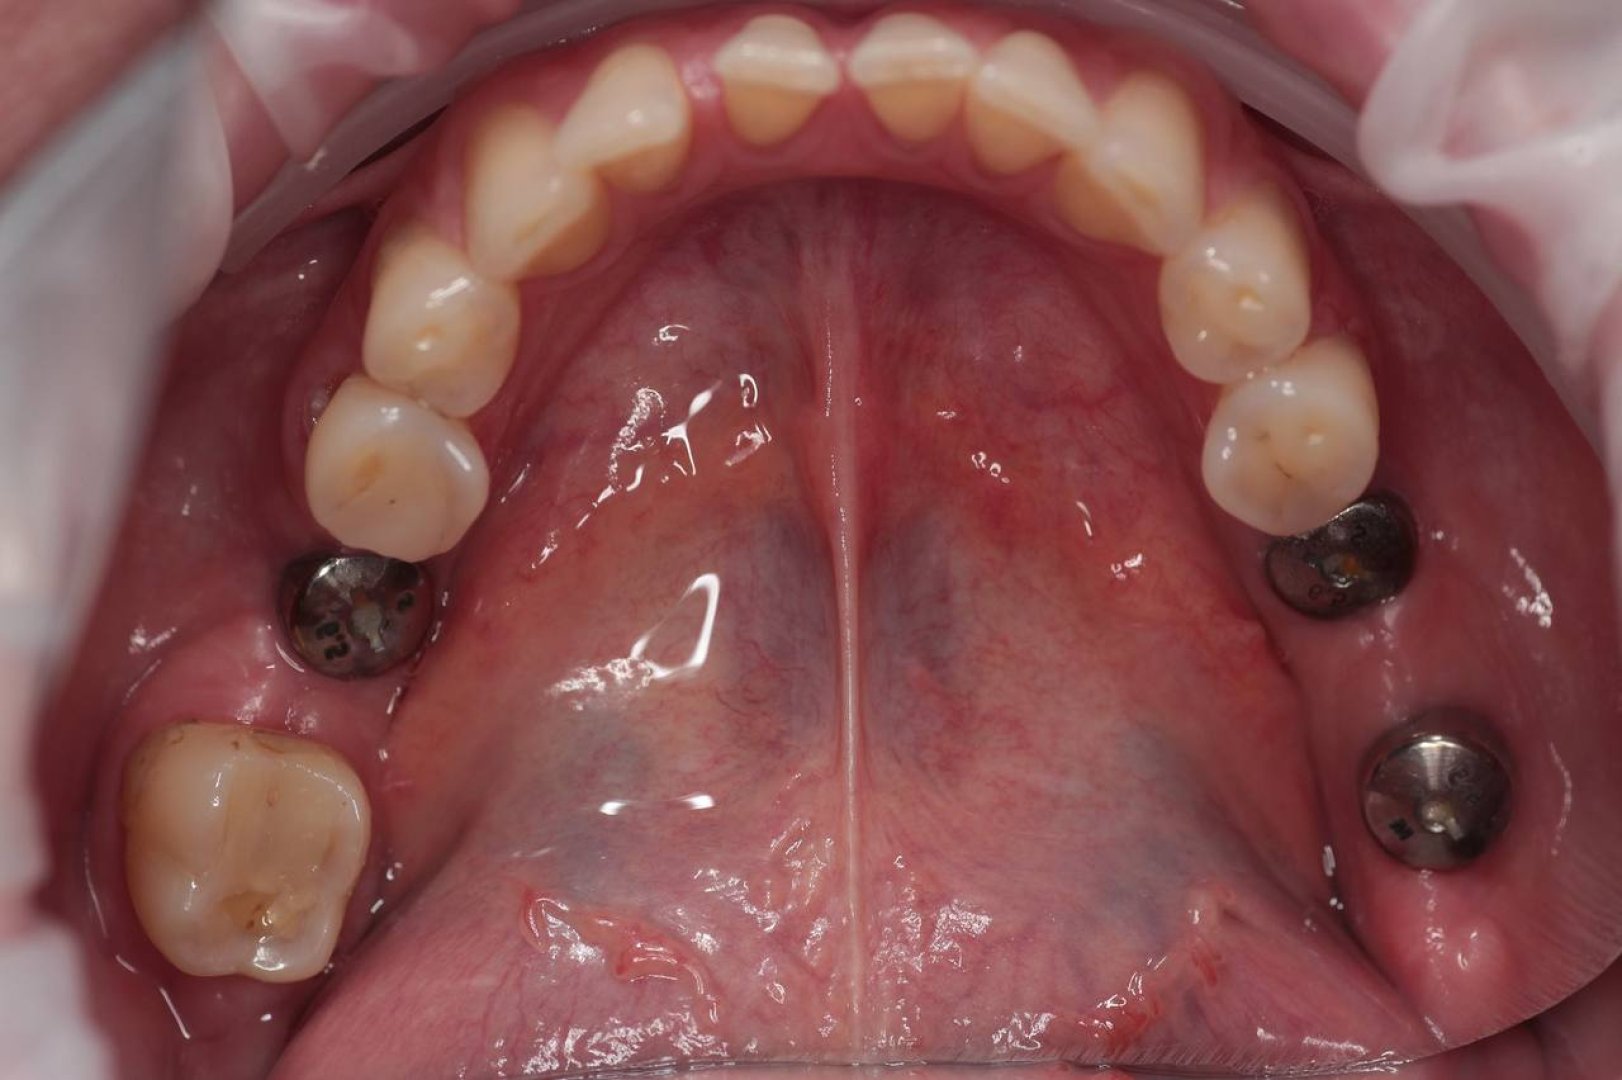

13,09,2025г, удалено 8 зубов на нижней челюсти, установлено 6 имплантов. 11,02,2026г, удалено 9 зубов на верхней челюсти, установлено 6 имплантов. Всё профессионально, чётко, в работе специалисты понимают дру друга с полуслова, это очень успокаивает в процессе операции. Огромное спасибо хирургу Благушиной Наталье Алексеевне, координатору по работе с клиентами Светлане, всему коллективу клиники! Благодарю Вас Всех!!!

На имплантах - вместо утраченного зуба

Коронка фиксируется на абатмент импланта.

Наши работы

На импланте вместо утраченного зуба. Имплант — это корень, коронка — это зуб. Одно без другого не работает.

Портфолио работ | Реальные кейсы

Смотрите «до/после» наших пациентов. Фотопротокол каждого случая.